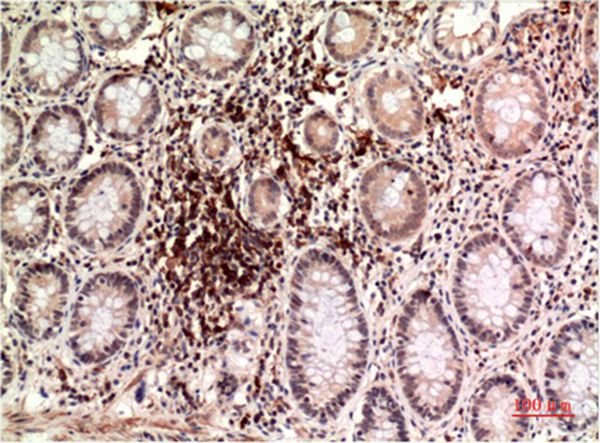

分类: 科研抗体货号: P43527别名: NLR family member X1 (Caterpiller protein 11.3) (CLR11.3) (Nucleotide-binding oligomerization domain protein 26) (Nucleotide-binding oligomerization domain protein 5) (Nucleotide-binding oligomerization domain protein 9)应用: WB,IHC反应种属: Human,Mouse,Rat